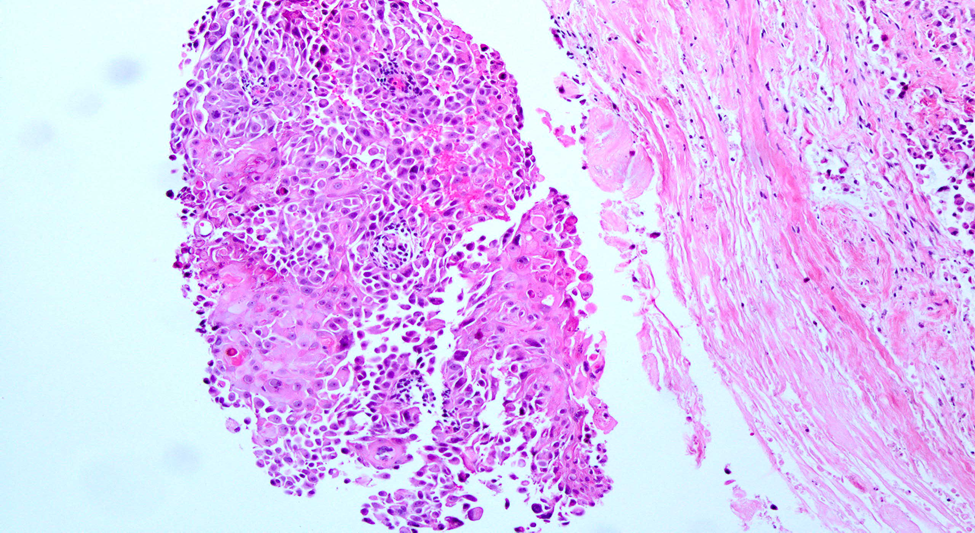

Then she underwent a Tru-cut biopsy which revealed a malignant neoplasm composed of poorly differential ductal with squamous differentiation.

Figure 2: Metaplastic carcinoma with squamous differentiation. Courtesy Huina Zhang, M.D, Ph. D.

Initially, chemotherapy was given. Then total mastectomy of the right breast was done. After the mastectomy of the right breast total breast including the nipple, skin, and axillary tail of the breast was sent for histopathology. Histopathological findings were metaplastic carcinoma with squamous differentiation, the tumor is classified as grade 2 with pT2N0MX and RCB class 2.

She underwent an ultra-sonogram of both breasts, the lump appeared as an irregular complex mass, after that mammography of both breasts along with tumor marker was done. Mammography showed BIRADS category 6 lesions. Then Tru-cut biopsy was done which revealed a malignant neoplasm composed of poorly differential ductal with squamous differentiation. Metaplastic breast cancers are triple negative and unresponsive to some useful chemotherapeutic agents. Breast conservative surgery and radical mastectomy are two surgical options for breast carcinoma. In metaplastic breast carcinoma, radical mastectomy is the treatment of choice. For this patient, radical mastectomy was performed, followed by a biopsy. The histopathology revealed that the patient had metaplastic breast carcinoma with squamous differentiation. The tumor is classified as grade 2 with pT2N0MX and RCB class 2.

Histopathological examinations revealed metaplastic breast carcinoma with squamous differentiation. In this case report, we have discussed a clinical presentation of metaplastic breast carcinoma with squamous differentiation.